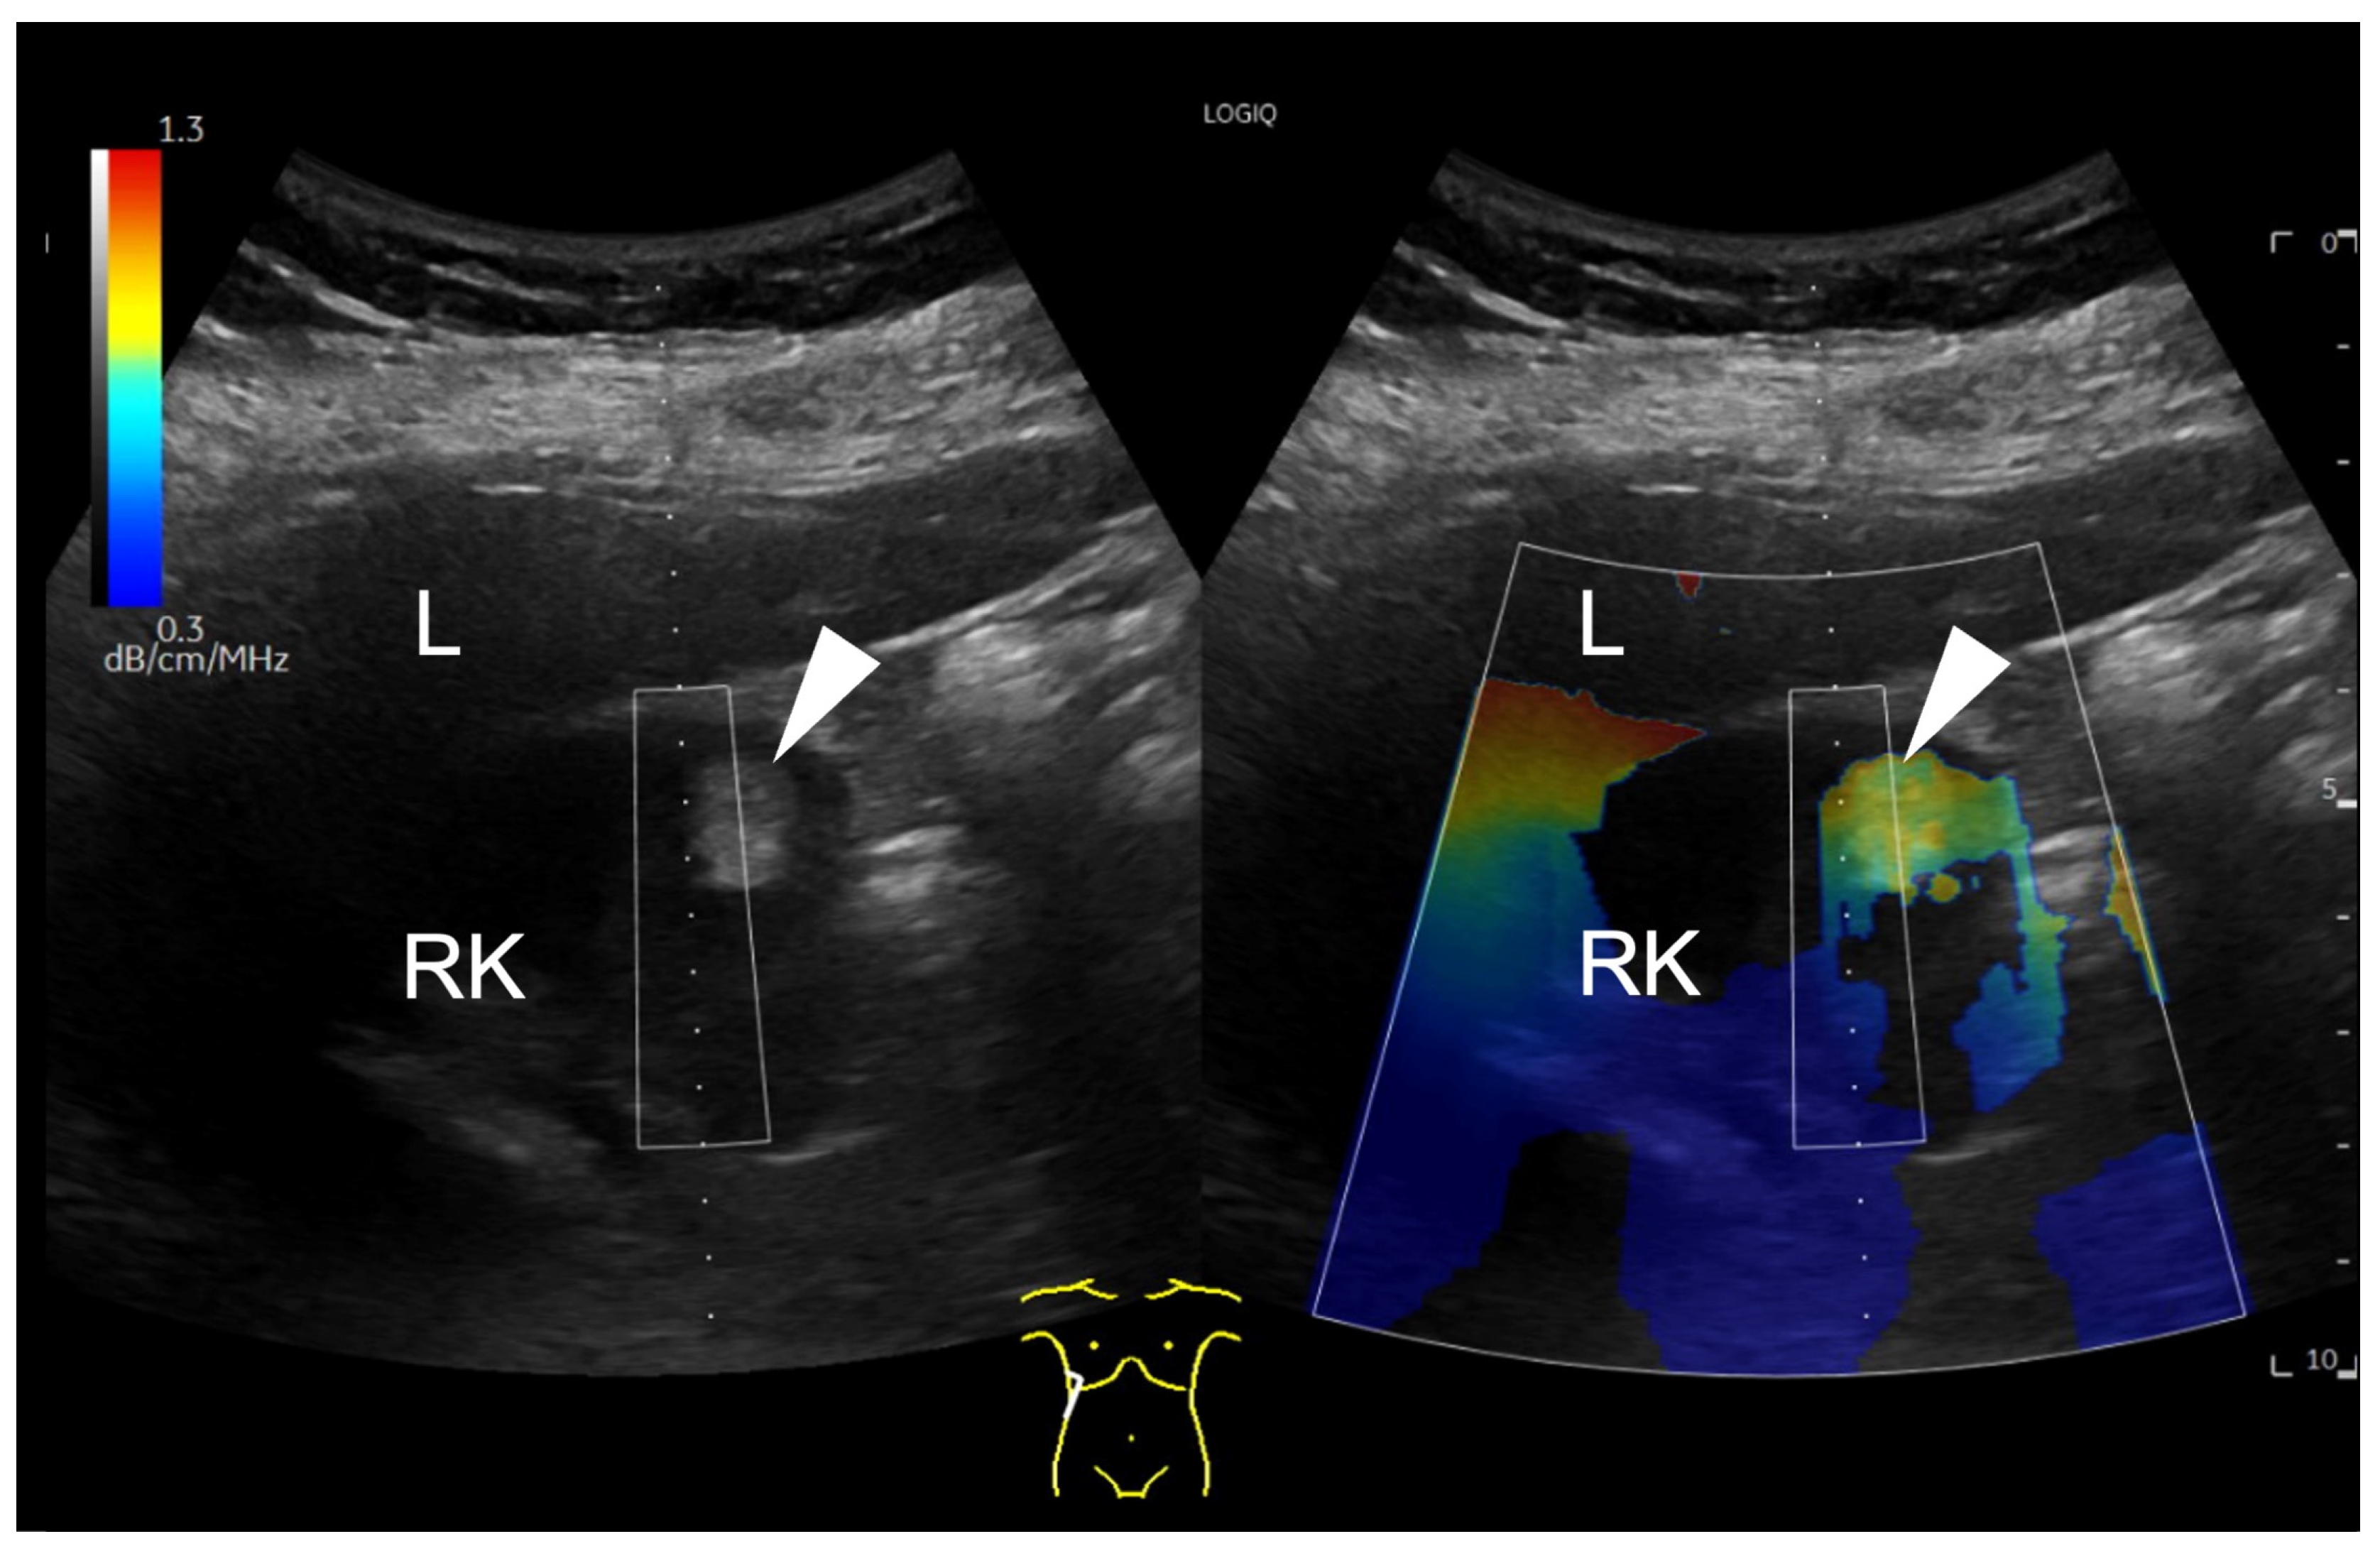

First, UGAP was used qualitatively. Using the quality map option, the color-coded map was placed right above the lesion. A positive finding was defined by a significant difference in the colour map above the lesion (red-yellow) compared to the surrounding tissue. This is shown for example in Figure 1.

Figure 1.

B-mode ultrasound image showing a focal hyperechoic lesion (arrowhead) in the cortex of the right kidney (RK). In the attenuation map on the right side, the lesion appears in red and yellow, representing a higher attenuation than the surrounding tissue. The level of attenuation is shown color-coded on the scale on the top left corner of the image. Next to the right kidney, the liver (L) is displayed. A region of interest (ROI) box is displayed above the hyperechogenic lesion.